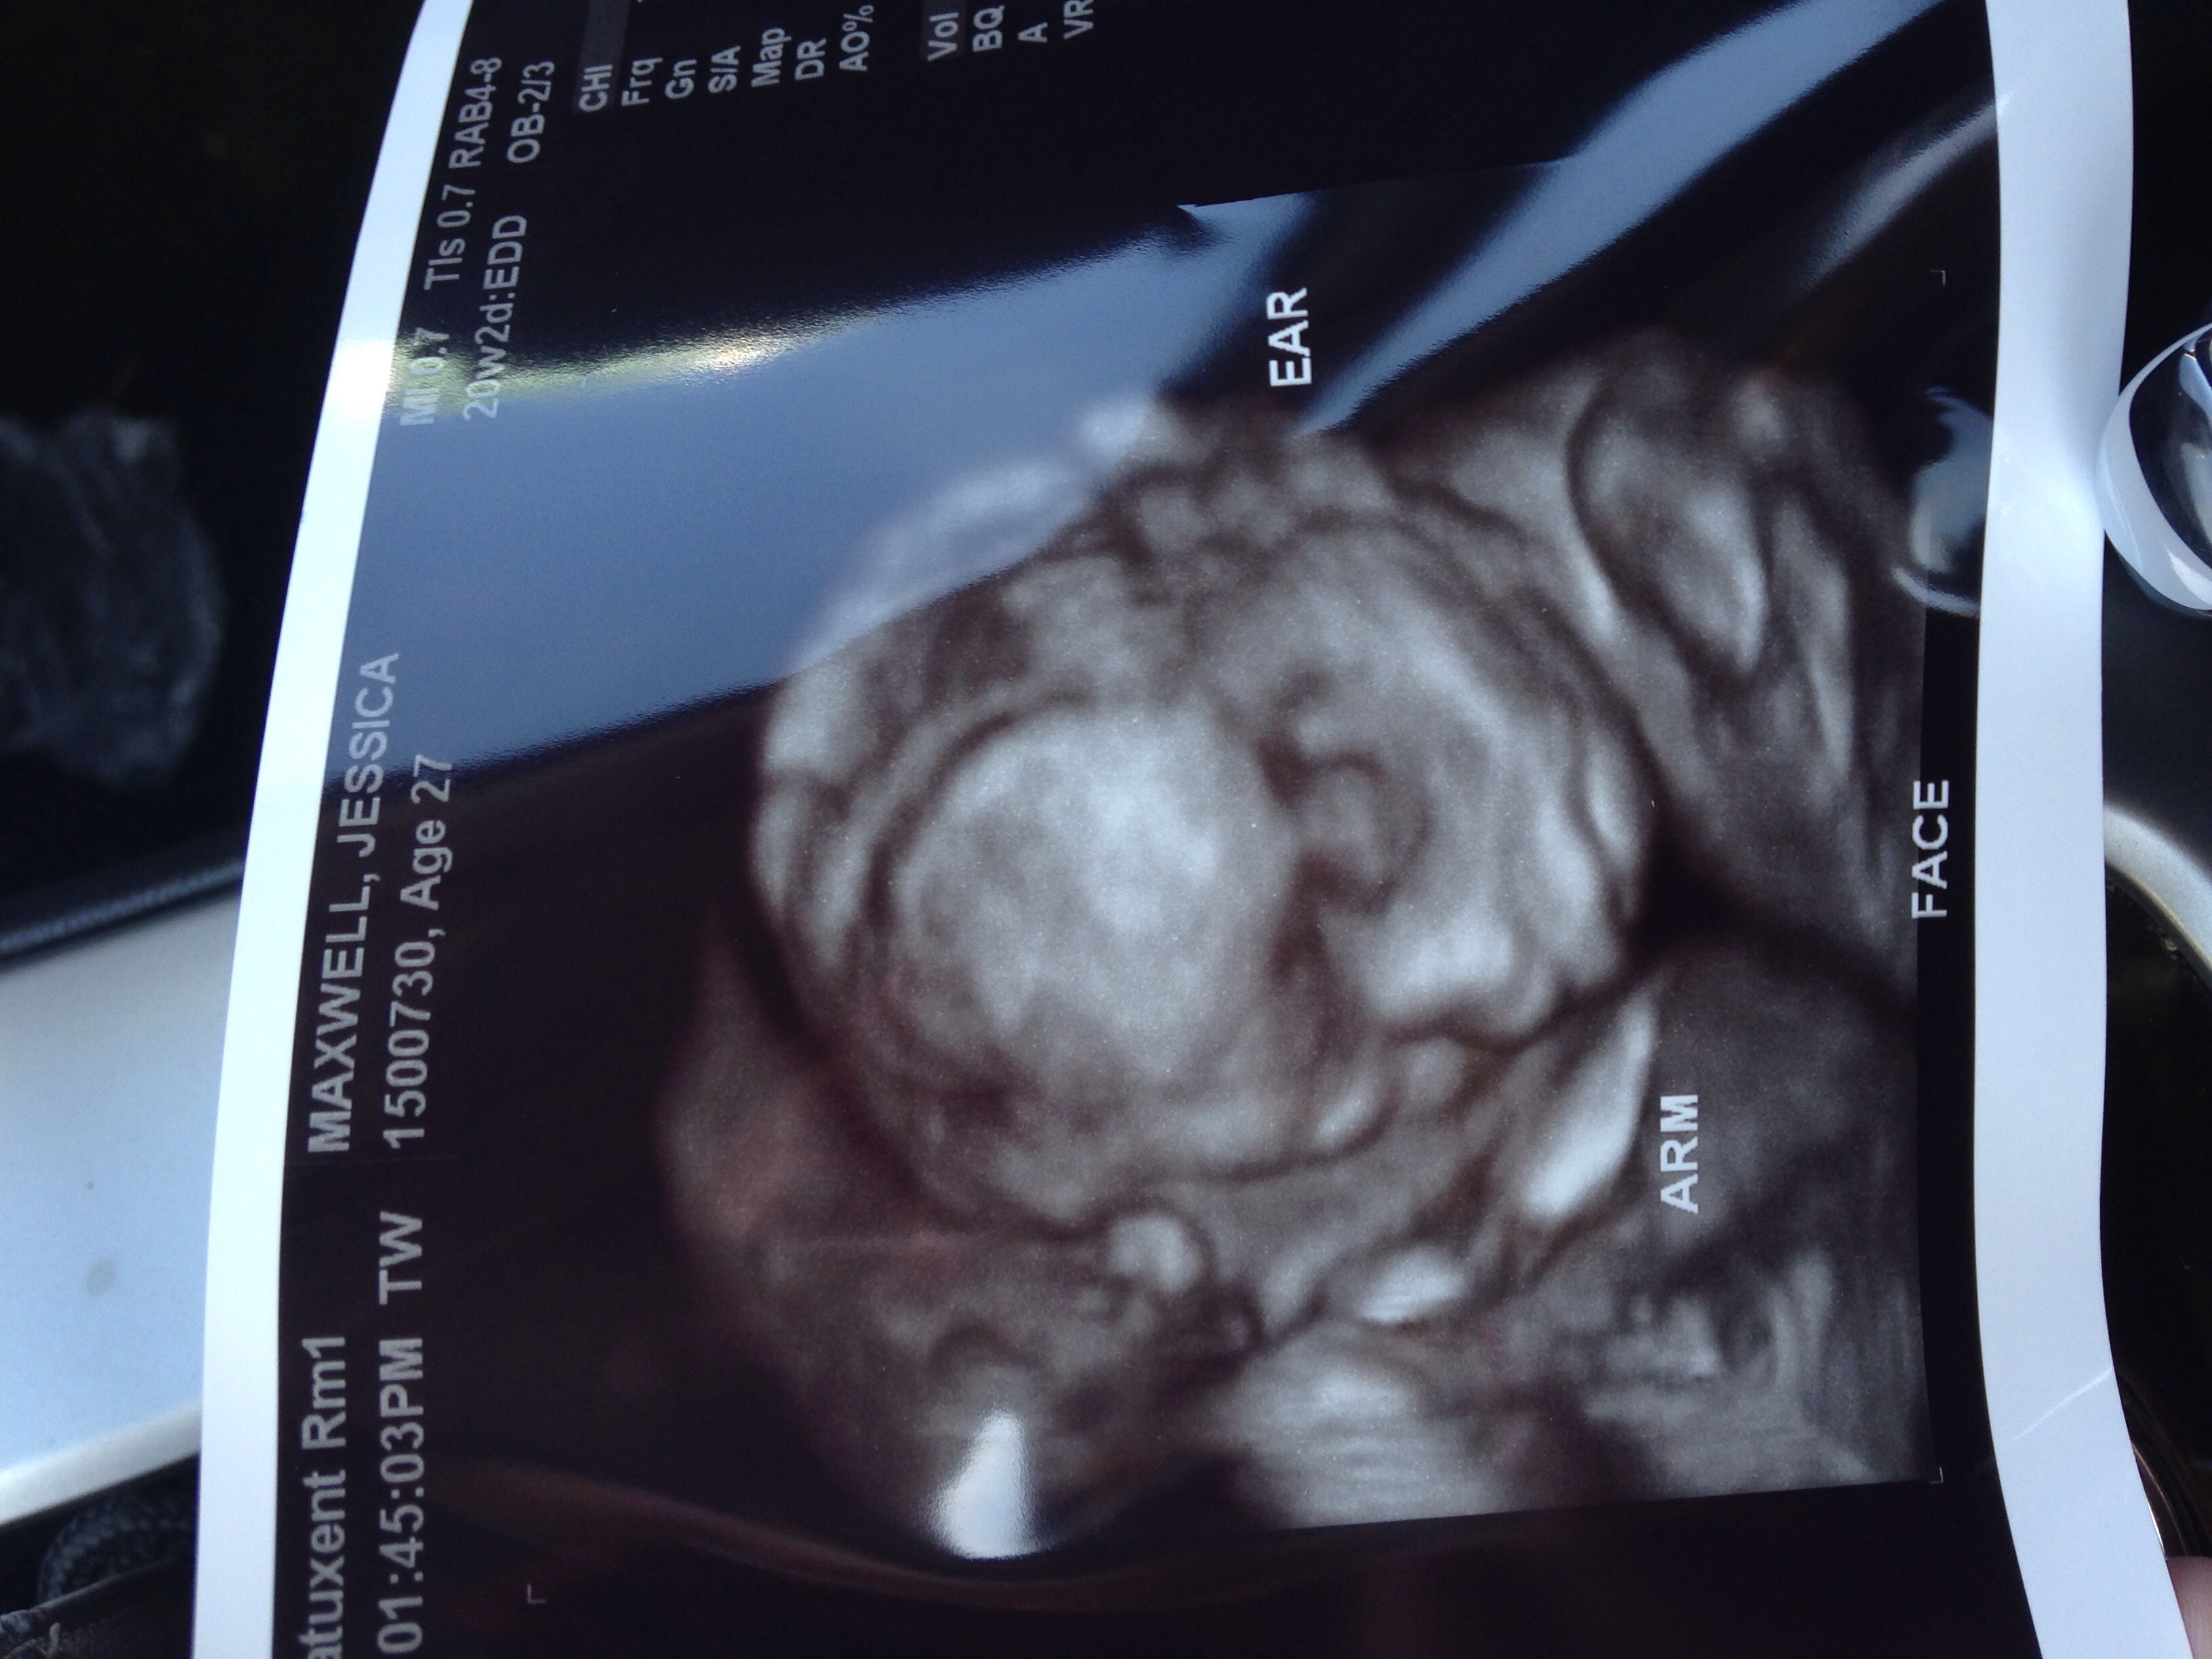

1st u/s pic at about 13w

2nd at 21w. Team blue! (Again!)

I'm so loving baby's little button nose! Can't wait to kiss it!